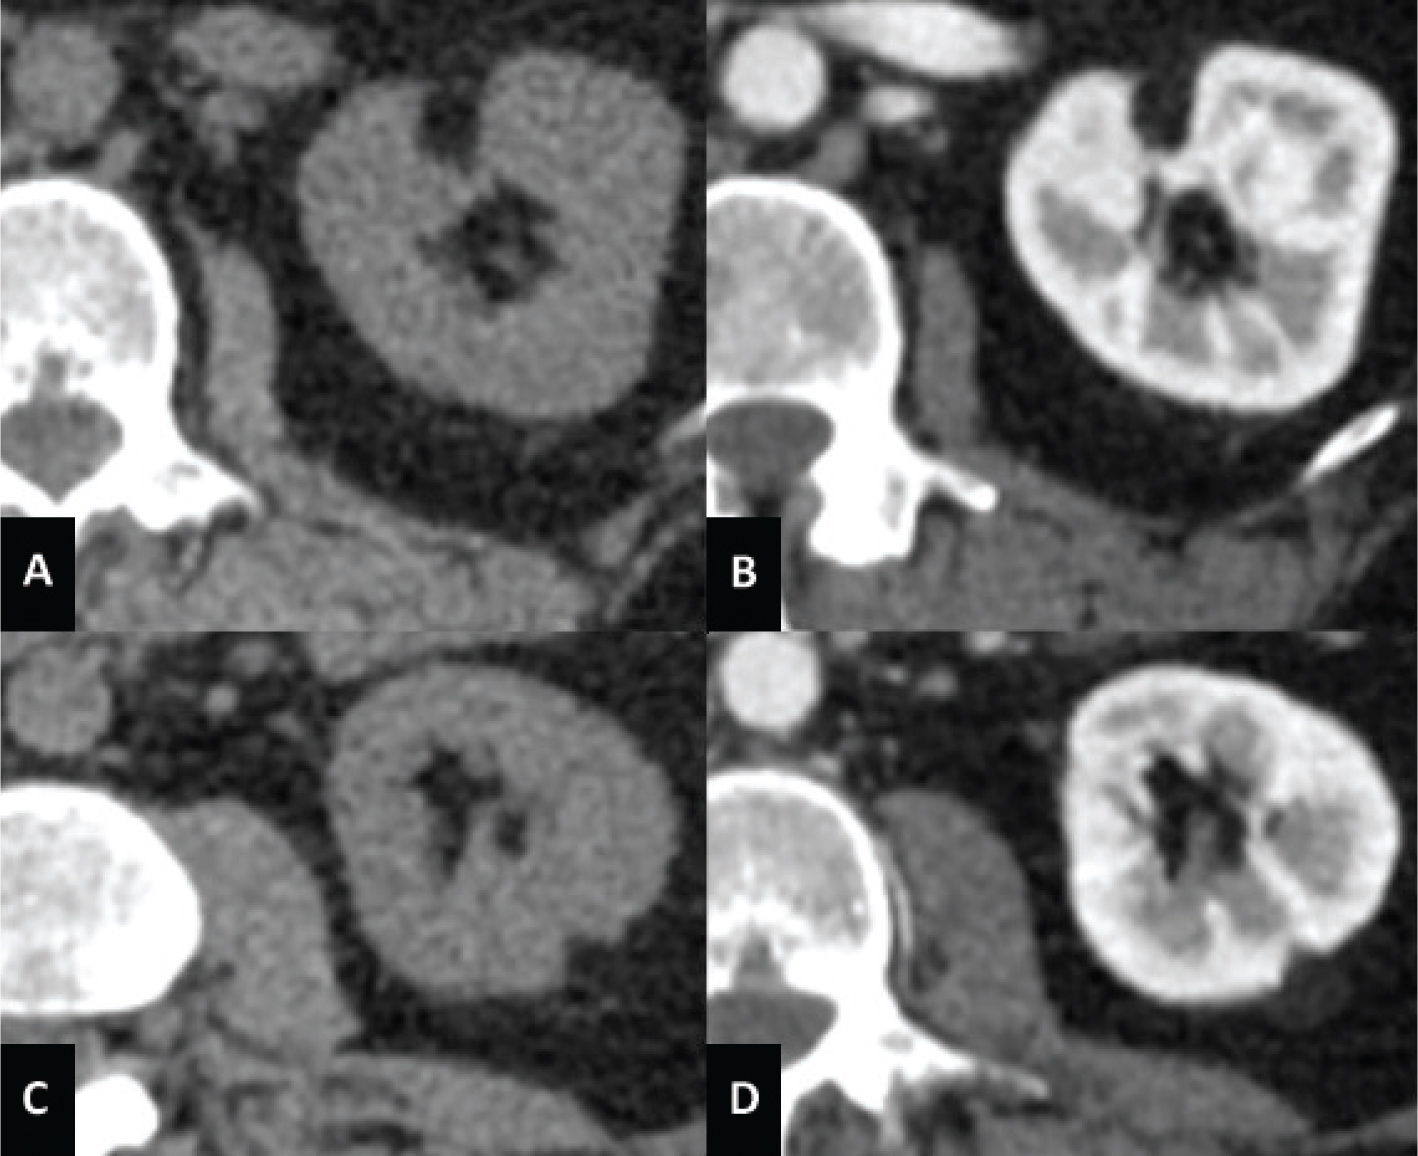

Fig 1

Figure 1. CT axial scan of the abdomen during venous phase of a 45-year-old woman with TS showing the presence of renal angiomyolipomatosis (A and B) and caliectasia at the level of the left upper calyceal group (A). Furthermore, a cystic lesion with solid peripheral tissue indissociable from the left inferior renal pole is evident (B). At the follow-up CT scan performed approximately 6 months later, the cystic lesion showed an increase of the solid component. Consequently, the patient underwent left nephrectomy and tumorectomy. Histological examination revealed the diagnosis of dedifferentiated liposarcoma.